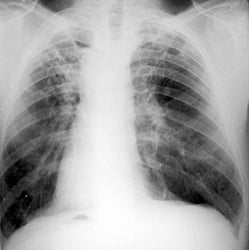

К числу эффективных диагностических методов, ориентированных на выявление туберкулезной инфекции, относятся:

- Флюорография грудной клетки;

- Рентгенография легких;